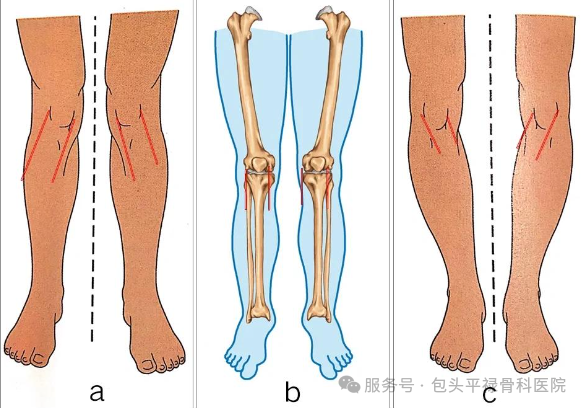

膝关节畸形不严重

内翻(O型腿)≤15度、外翻(X型腿)或屈曲畸形≤10度,且可被动矫正。

对术后关节活动度要求较高的较年轻患者,单髁置换常能提供更接近自然关节的运动感觉。若关节炎已累及多间室、韧带严重损伤失效、关节畸形僵硬严重,则全膝关节置换通常是更合适的选择。